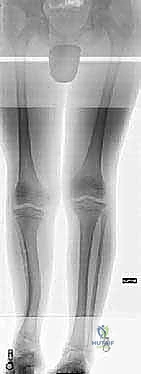

1. التقييم والتخطيط قبل الجراحة (Pre-operative Planning)

يتم إجراء فحص سريري شامل للمريض، متبوعاً بصور أشعة سينية بانورامية (Scanogram) لقياس طول العظام بدقة مليمترية. يقوم الدكتور هطيف باستخدام برامج تخطيط ثلاثية الأبعاد لتحديد نقطة القطع العظمي ونوع الجهاز الأنسب (إليزاروف أم أحادي المستوى).